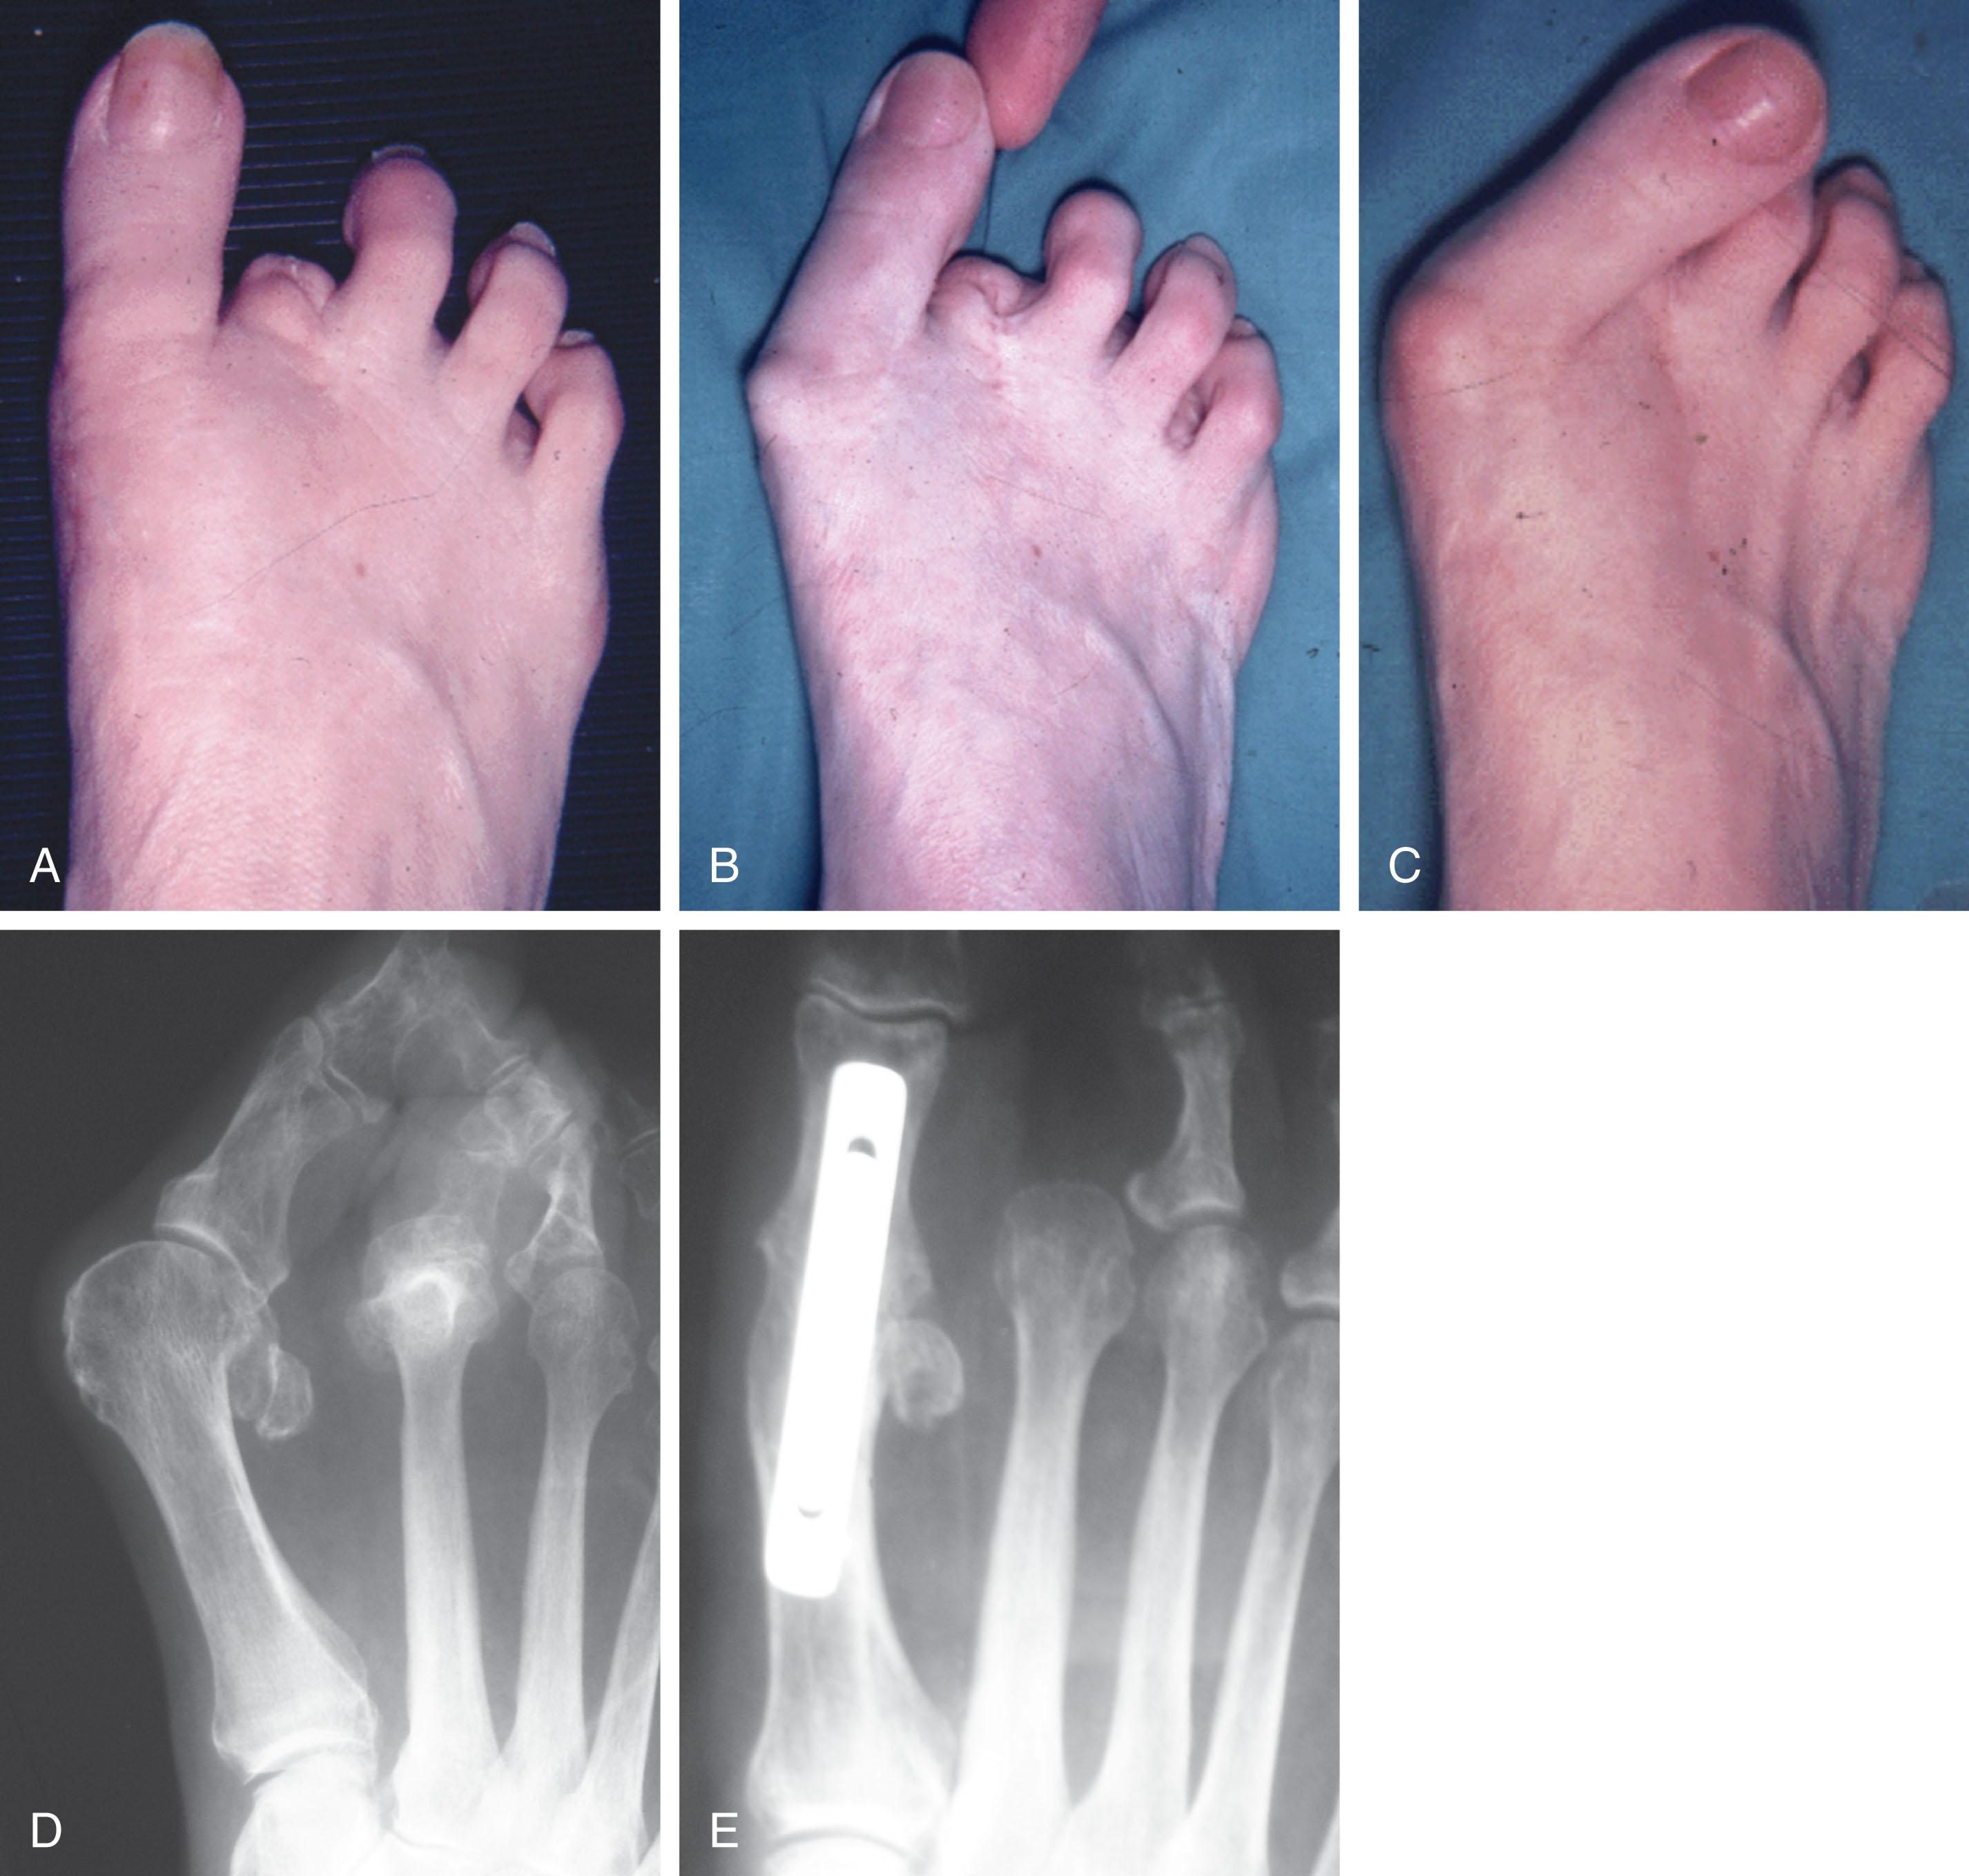

Partial proximal phalangectomy has been recommended by Johnson and others ( Figs. 9-50 and 9-51 ) as a treatment for a hammer toe deformity in association with MTP joint deformity. Cahill and Connor reported on 78 patients (84 toes). They noted poor objective results in 50% of patients and concluded that partial proximal phalangectomy relieved symptoms but left a cosmetically poor result ( Fig. 9-52 ). Conklin and Smith noted a 29% postoperative dissatisfaction rate; major complaints were shortening of the ray, floppiness of the toes, metatarsalgia, weakness, and stiffness.

Fig. 9-50, With a partial proximal phalangectomy, the base of the proximal phalanx is excised. Often, adjacent partial proximal phalangectomies are performed in combination with syndactylization. A and B , An intramedullary web space incision is made to approach the adjacent metatarsophalangeal joints. C , The bases of the proximal phalanges of the second and third toes have been excised. D–F , Closure of deep and superficial tissue.

Fig. 9-51, A , Painful degenerative arthritis of the second metatarsophalangeal joint. Radiograph demonstrates complete loss of the remaining joint space. B , After excision of the base of the proximal phalanx of the second toe, an intramedullary Kirschner wire is used to stabilize the repair until adequate healing is achieved. C , Intraoperative photograph after partial proximal phalangectomy. D , After removal of Kirschner wire.

Fig. 9-52, A and B , Intraoperative photographs after Kirschner wire fixation and syndactylization after partial proximal phalangectomy of the second toe deformity. C , Radiograph immediately after surgery. D , A radiograph 5 years postoperatively demonstrates severe shortening of the proximal phalanx with a varus deformity of the third toe. E , Cosmetically unacceptable syndactylization after partial proximal phalangectomy of only the second toe.

A limited syndactylization may be combined with a partial proximal phalangectomy of adjoining phalanges. Daly and Johnson reported 75% patient satisfaction with this procedure; however, 43% of patients had moderate footwear restrictions, 27% reported residual pain, 28% noted moderate or severe cosmetic problems, and 18% reported a recurrent cock-up deformity. In general, the treatment of a hammer toe deformity by creating another deformity with a partial proximal phalangectomy and syndactylization should be discouraged except in a salvage situation.

Amputation of the second toe may be an expeditious treatment for severe deformity in an elderly patient, but it is ill-advised in a younger patient because a hallux valgus or other toe deformity can progress ( Fig. 9-53A, C, and D , Fig. 9-54 ). Ely believed a hallux valgus deformity would not progress after amputation of a second toe. VanderWilde and Campbell reported on 16 patients (22 feet) who underwent a second toe amputation. They observed mild progressive drift of the hallux but thought that it was usually not significant. Despite these reports, it is generally accepted that removal of the second toe can place the patient at risk for a progressive hallux valgus deformity in time. Arthrodesis of the hallux MTP joint may be combined with a second toe amputation to ensure that a hallux valgus deformity will not progress with time ( Fig. 9-53E and F ). Gallentine and DeOrio reported on 17 amputations in patients averaging 78 years of age; 14 of 17 had a severe hallux valgus deformity, and absence of the toe was not an issue for them. They reported this to be a simple procedure with a predictable healing and recovery (see Fig. 9-54 ).

Fig. 9-53, A , After amputation of second toe. B and C , Progressive hallux valgus after amputation of second toe. D , Preoperative radiograph with hallux valgus and dislocated second metatarsophalangeal (MTP) joint. E , After MTP fusion and second toe amputation.